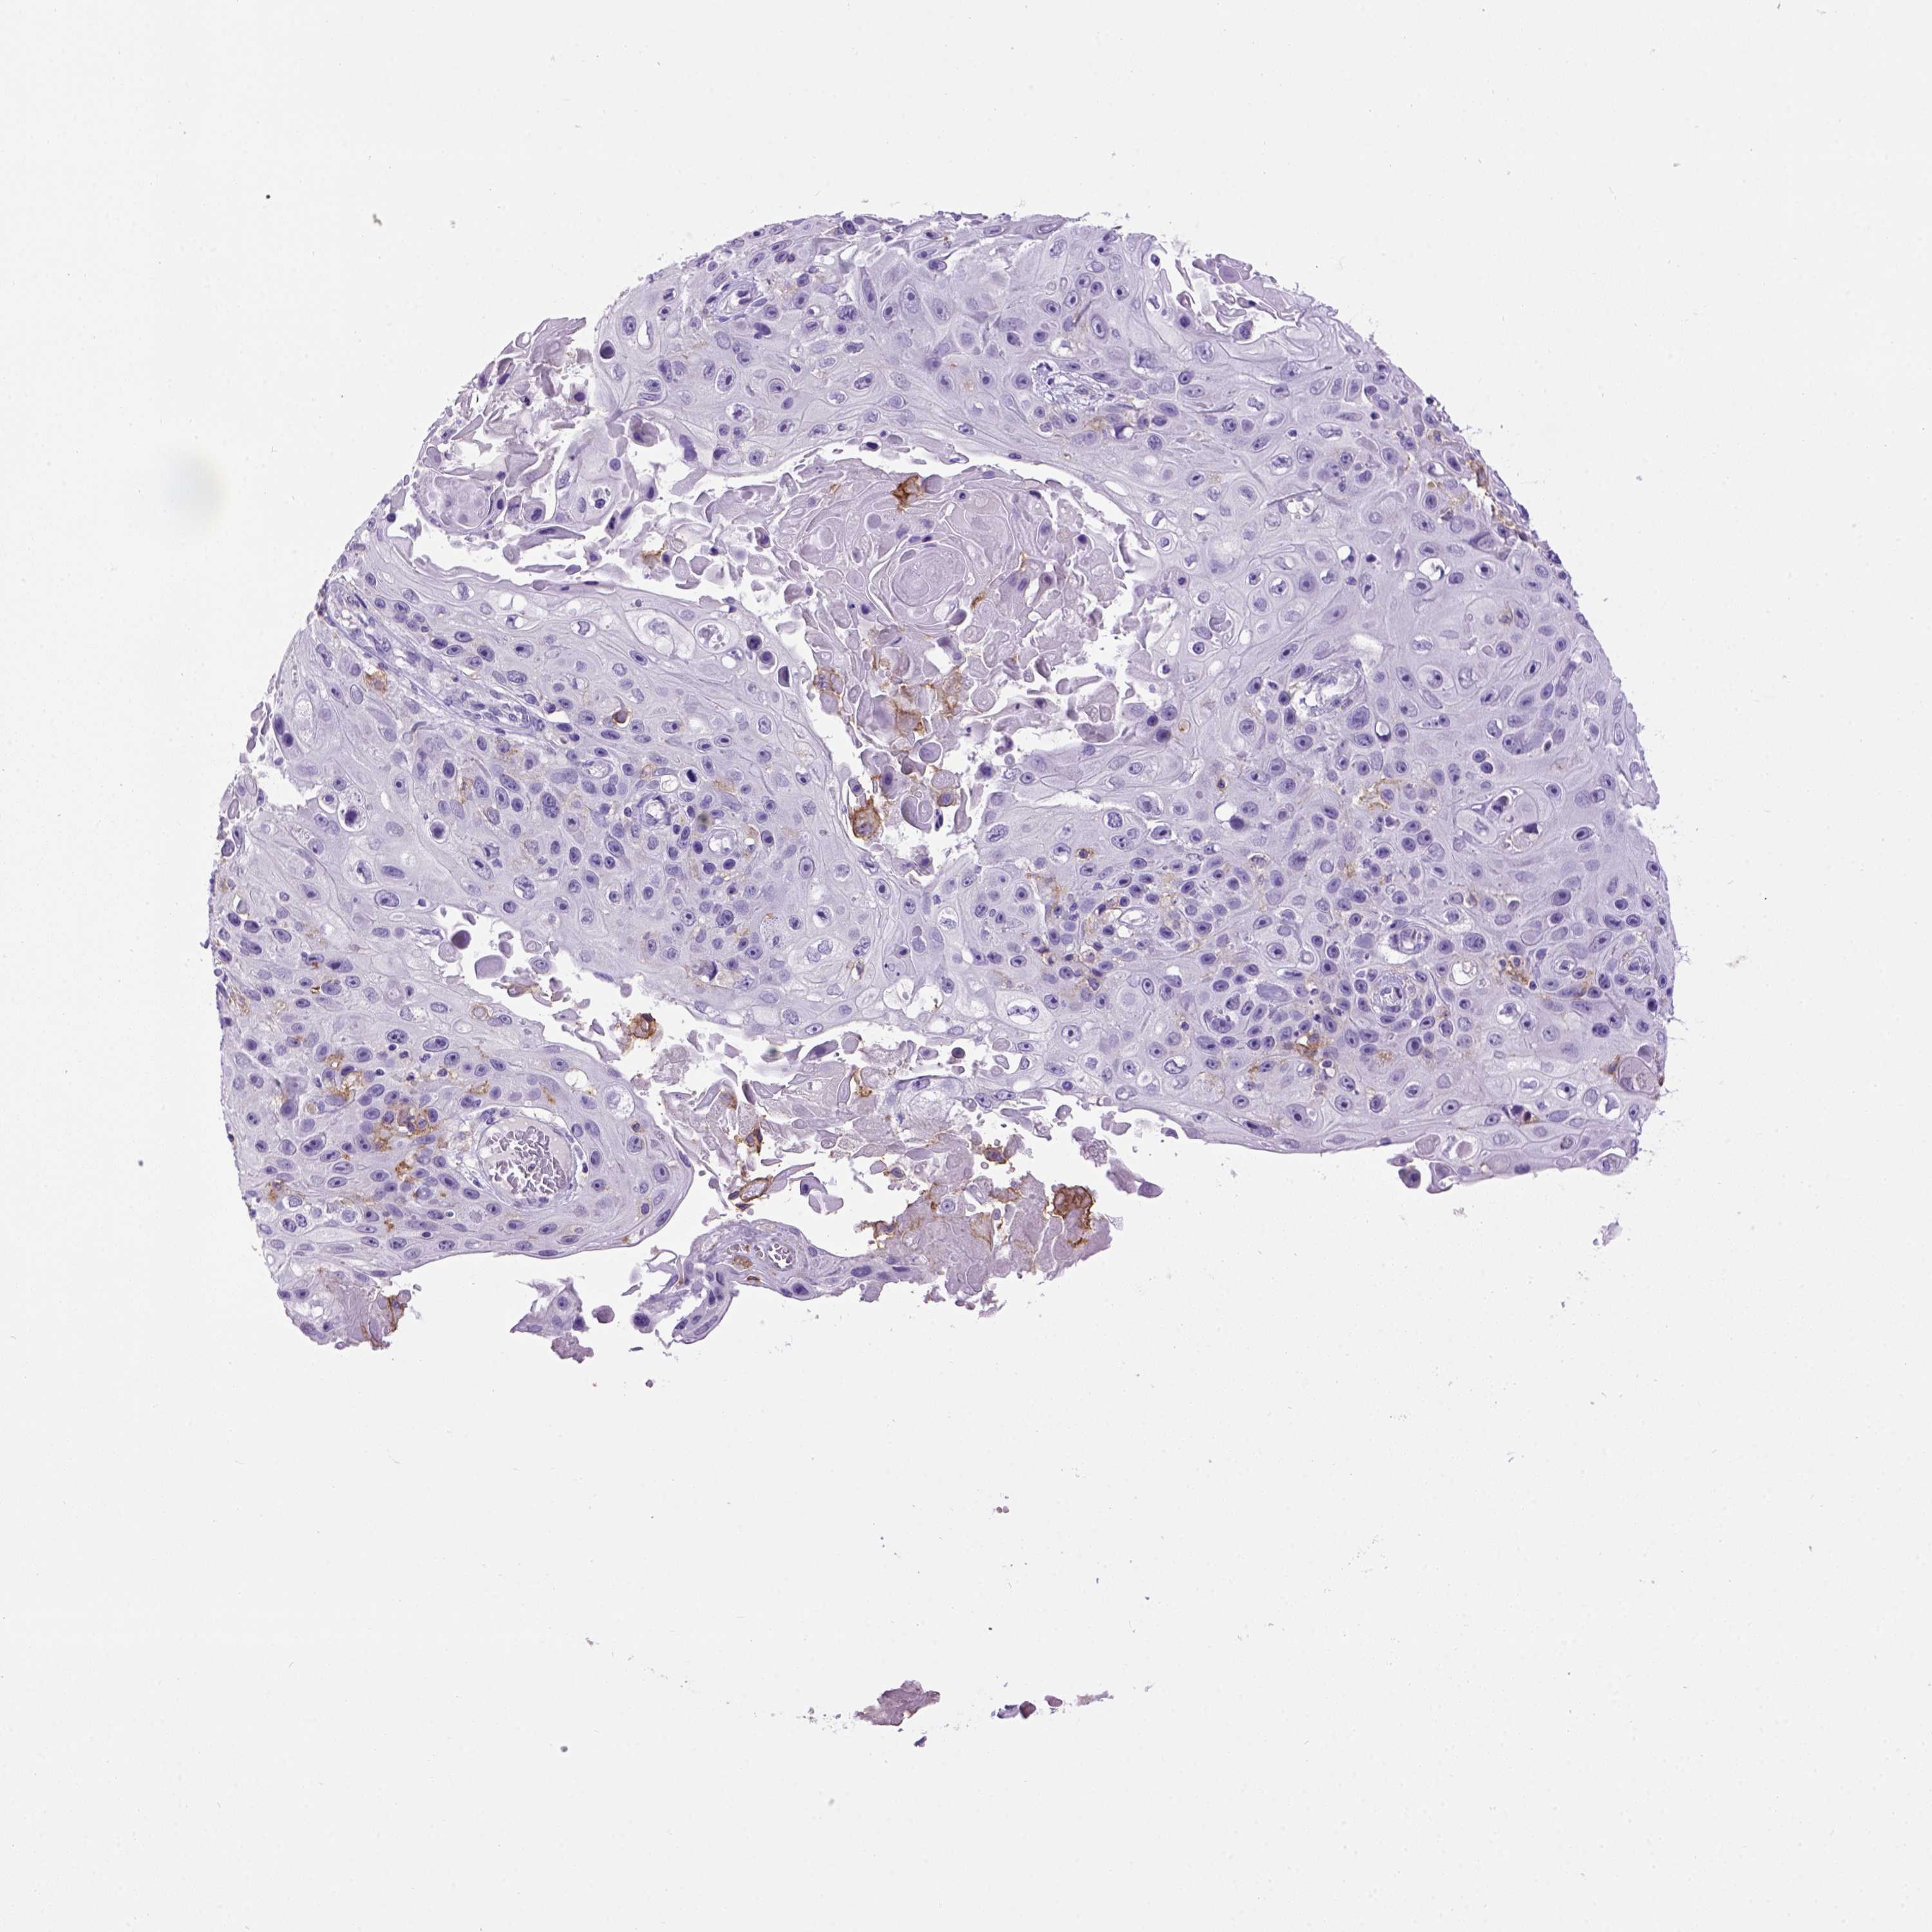

CANCER SKIN CANCER Show tissue menu

Basal cell and squamous cell cancer

SKIN CANCER - Protein expressioni

A mouse-over function shows sample information and annotation data. Click on an image to view it in a full screen mode. Samples can be filtered based on level of antibody staining by selecting one or several of the following categories: high, medium, low and not detected. The assay and annotation is described here.

Antibody staining in the annotated cell types in the current human tissue is reported as not detected, low, medium, or high, based on conventional immunohistochemistry profiling in selected tissues. This score is based on the combination of the staining intensity and fraction of stained cells.

Each image is clickable and will lead to virtual microscopy that enables deeper exploration of all samples and also displays staining intensity scores, fraction scores and subcellular localization as well as patient and tissue information for each sample.

Squamous cell carcinoma, NOS